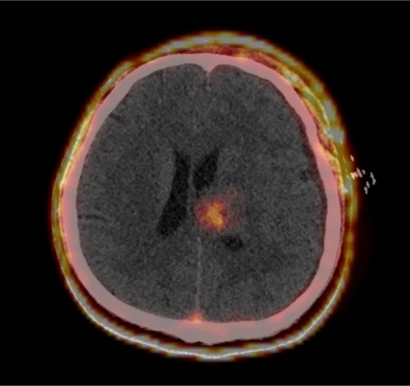

PET/CT可以在分子层面诊断肿瘤代谢、肿瘤相关成纤维细胞等相关分子

肿瘤微创治疗之所以微创就是对病灶实施精确打击,PET/CT好比相控阵雷达,可以清晰分辨异常和正常组织